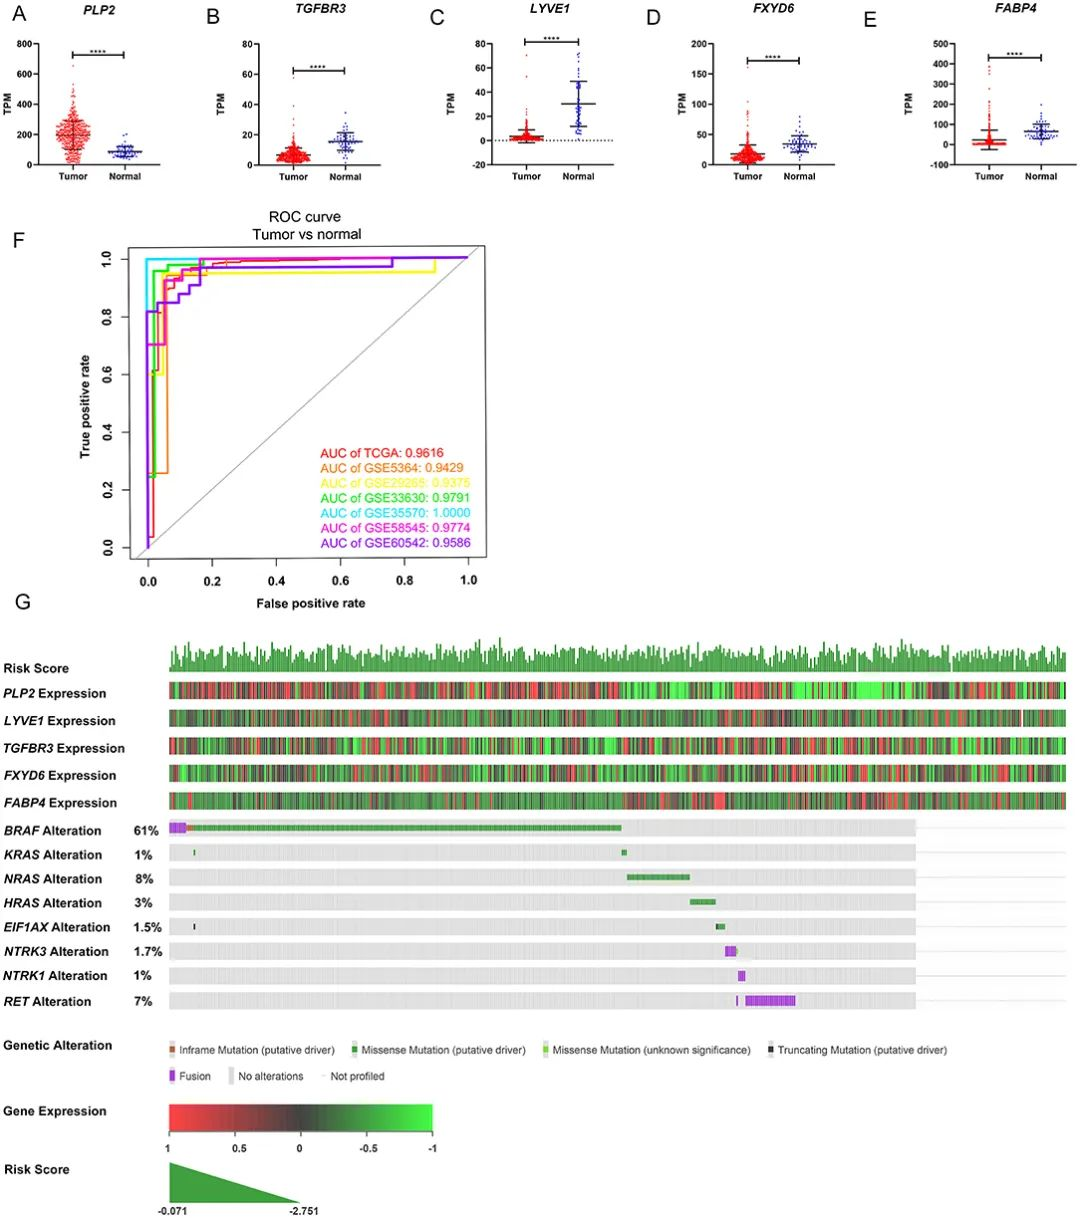

数据分析与作图

滑动查看更多 点击查看大图